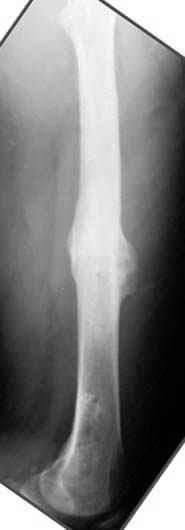

пластическая модель; и коррекция бедра аппаратом Илизарова.